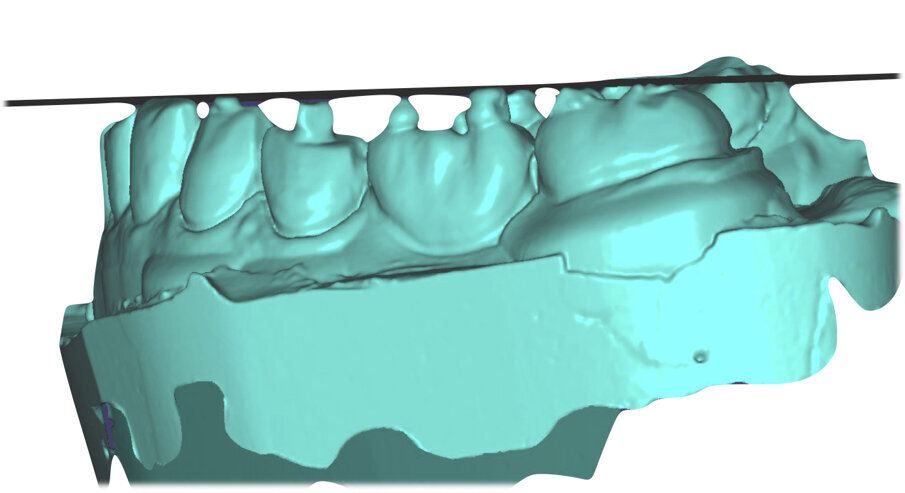

Si esegue perciò cefalometria (Fig. 8) su radiografia latero-laterale (Fig. 9) e axiografia dei movimenti limite (Cadiax Compact, Gamma Dental) (Fig. 10) per la programmazione di un articolatore a valori medi (Artex TR, AmmanGirrbach) e montaggio dei modelli con arco faciale, che confortano nella produzione di un primo provvisorio prelimatura con rialzo arbitrario della VDO di 5 mm sull’asta incisale e miglioramento di OB e OJ, a scopo pre-terapeutico interlocutorio e di immediata risoluzione estetica. Conclusa la necessaria terapia causale e restaurativa viene eseguita la scansione intraorale delle arcate (TRIOS 3 Pod, 3Shape) (Figg. 11-14) e del rapporto articolare con cera di RP (Fig. 15). La scansione è stampata (VisiJet RWT, 3D Systems) con monconi sfilabili tramite stampante 3D (ProJet MJP 2500 Plus, Selltek) (Figg. 16-20), i modelli derivanti sono zoccolati e montati con cere di RP e arco faciale su articolatore a valori individuali (Reference SL, Gamma Dental). La programmazione dell’articolatore derivante dalla registrazione axiografica è ora eseguita come da indicazioni del software (Gamma Dental software, sia per l’uso degli inserti condilari ed incisali, sia per la definizione degli angoli di SCI e di Bennet (Fig. 21). Lo spazio protesico risultante a una VDO adeguata alla riabilitazione dei denti anteriori vitali, con anatomia non ulteriormente modificabile, è insufficiente per uno stabile ripristino dei rapporti occlusali, specie nei tragitti funzionali. Si decide perciò di impiegare due inserti rossi di programmazione di protrusiva (+2 mm) per riposizionare la mandibola in TRP (Figg. 22, 23).

Ciò consente un miglioramento dei rapporti interarcata, un guadagno di spazio protesico in regioni premolari e molari, ed il mantenimento di uno spazio protesico conforme ad una corretta anatomia per i denti vitali da 1.3 a 2.3. Al paziente viene pertanto aggiornato il piano di trattamento e proposta la riabilitazione in TRP, con la previsione di overlays all’arcata inferiore per costruzione del nuovo piano occlusale. In posizione terapeutica sono modellati i coni delle centriche attive sui monconi sfilabili all’arcata inferiore, per la successiva individuazione al CAD con modulo articolatore del piano occlusale studiato. Questo rapporto articolare in TRP è ora scansito con scanner da laboratorio Xanos Evo Scan Compact (Fig. 24).

I modelli sono così importati in corretta posizione spaziale tramite il modulo exocad Virtual Articulator (Fig. 25). Non avendo a disposizione nel CAD l’analogo virtuale dell’articolatore Reference SL, viene impostato il sistema virtuale SAM, che usa lo stesso piano di riferimento axio-orbitale e geometria sovrapponibile al Reference SL. Per la programmazione virtuale dei parametri funzionali dell’articolatore si riesegue l’output dall’axiografia elettronica con Gamma Dental per SAM (Fig. 26). Si procede perciò ora con la modellazione CAD della ceratura mantenendo il riferimento dato dal piano occlusale individuato dai coni di centrica scansiti con l’articolatore (Fig. 27). L’articolatore virtuale consente una prima verifica dei rapporti occlusali tra gli elementi e un abbozzo di funzionalizzazione delle cuspidi con strumenti virtuali dinamici, che permette di arrivare ad un CAD design vicino alla morfologia ricercata (Figg. 28-33). Il modellato è ora fresato in cera Yeti Dental al CAM con fresatore VHF Cam5-S1 ed i denti in cera, tutti singolarmente sfilabili, sono posizionati sui modelli eseguiti con stampa 3D.